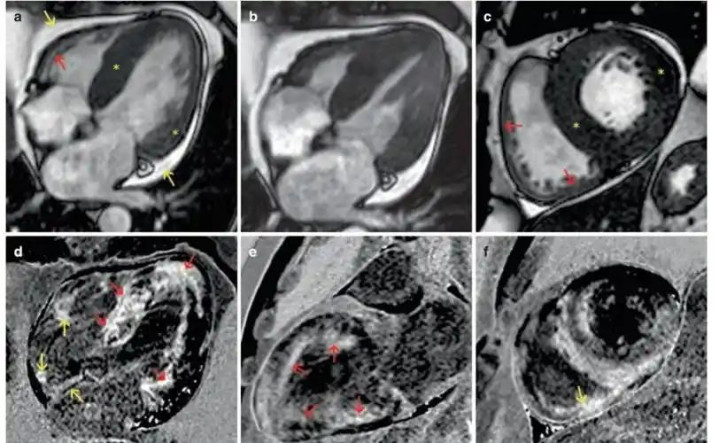

2. 心肌防护与存活率评估

打针含钆的造影剂后,不错不雅察心肌在不同情景(静息或药物负荷下)的血流防护情况,从而判断是否存在心肌缺血。更迫切的是,在打针造影剂5-10分钟后进行的蔓延增强扫描,不错特地精确地披露心肌梗身后的疤痕组织(纤维化),这些区域会呈现亮白色,而健康心肌则为暗色。这一信息对于判断受损心肌是否还有存活价值、以及是否需要作念支架或搭桥手术至关迫切。